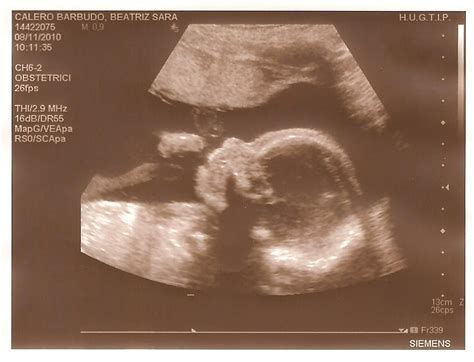

Ecografia 4D HD embarazo de 23 semanas cara durmiendo Dr ...

Ecografia 4D HD embarazo de 23 semanas cara durmiendo Dr ... from i.ytimg.com